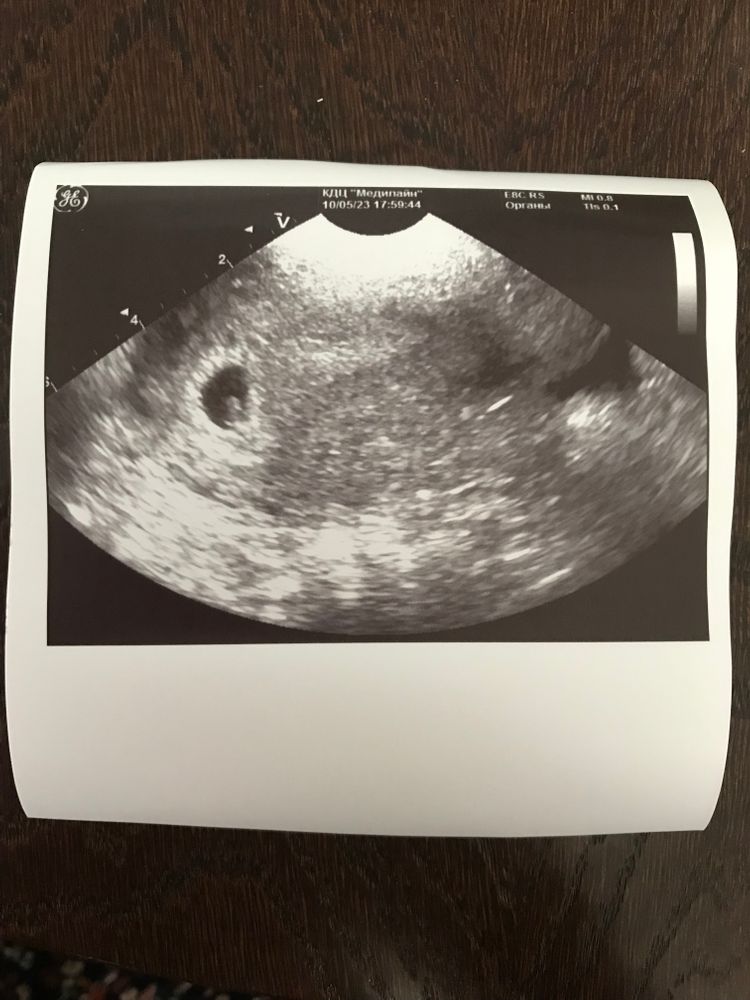

Первое УЗИ. 6 нед .

А это наше первое фото.